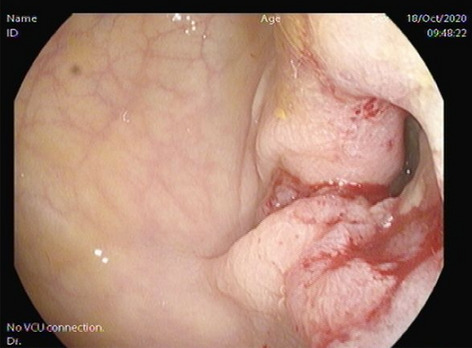

Colorectal—Malignant

O193—The role of 3D modelling technology in recognition of colorectal tumour deposits

Aims: 3D modelling technology is rapidly gaining interest in various fields of surgery. It can be used for operative planning and navigation, as well as surgical education and patient interaction. It allows for depiction of complex anatomical relationships in a more comprehensible way than traditional radiological images. However, it also has potential to become a tool facilitating gaining further understanding of surgical pathology by allowing to display and analyse imaging data in a new way. Tumour deposits are a challenging entity. They are currently being closely investigated with an aim to develop understanding of their role in colorectal cancer spread. It is an ever evolving concept which requires further research to fully appreciate the origin and significance of tumour deposits. We applied the novel 3D modelling technology to illustrate tumour deposits in colorectal cancer.

Methods: 3D virtual models were created through manual segmentation of CT and MRI scans obtained according to protocols routinely used in colorectal cancer staging. No extra patient time or preparation were needed. CT and MRI images were analysed by Gastrointestinal Radiologist to delineate the tumour and provide the cancer staging. Manual segmentation was then performed in 3D Slicer, an open-source, free software used for creation of three-dimensional anatomical models. Additional post-processing was applied in MeshLab or Blender.

Results: Ten 3D models depicting tumour deposits in colorectal cancer were created. Models of right- and left-sided bowel cancer with tumour deposits were derived from CT scans, while those of rectal cancer—from MRI scans. 3D models depicted bowel with the tumour and tumour deposits, relevant vasculature and lymph nodes, as well as surrounding structures as required. Models can be manipulated to allow for most comprehensible inspection of different anatomical structures and relationships. The transparency of each structure can be changed. The morphological appearance of tumour deposits and their relation to vessels can be readily appreciated. The morphological differences between the tumour deposits and lymph nodes, both benign and metastatic, can also be evaluated.

Conclusions: This work follows on from our previous experience with exploration of 3D modelling technology to map tumour deposits in rectal cancer, based on rectal MRI images. This innovative technology shows a huge potential to enhance our understanding of surgical pathology. It can provide a welcome assistance in exploring new concepts and developing new theories. It can facilitate communication and discussion around the evolving concepts. It is a versatile novel tool which can be successfully applied for depiction of tumour deposits in any part of the bowel. Here we showed its feasibility for the use in left- and right-sided bowel cancer, in addition to previously explored rectal cancer. It can utilise modalities commonly used in colorectal cancer staging – CT and MRI, which renders it clinically applicable. While there is an ongoing debate on the correct classification of tumour deposits and their full significance in metastatic process, as well as their prognostic value, 3D technology can facilitate familarisation with their appearance. It can also become an educational tool both for radiologists and surgeons and a valuable adjunct in the multidisciplinary management of colorectal cancer.